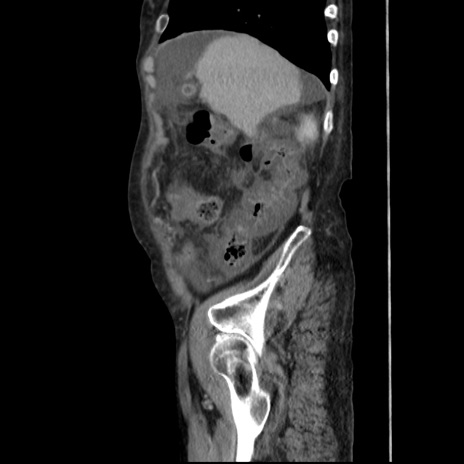

症例31(矢状断像)

【症例】80歳代 女性

【主訴】腹部膨満感

【現病歴】他院にて肝硬変にてフォロー中。1週間前から便秘、腹部膨満感、臍部腫瘤あり受診となる。

【既往歴】肝硬変

【身体所見】腹部膨隆あり、皮膚変化なし、疼痛なし。

【データ】WBC 4600、CRP 0.25